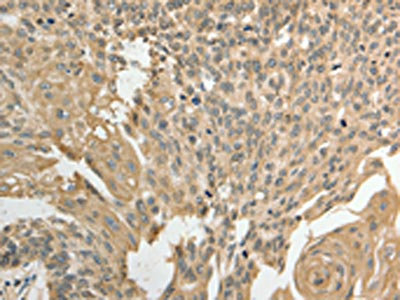

The image on the left is immunohistochemistry of paraffin-embedded Human cervical cancer tissue using CSB-PA436998(GSR Antibody) at dilution 1/50, on the right is treated with fusion protein. (Original magnification: ×200)

The image on the left is immunohistochemistry of paraffin-embedded Human ovarian cancer tissue using CSB-PA436998(GSR Antibody) at dilution 1/50, on the right is treated with fusion protein. (Original magnification: ×200)